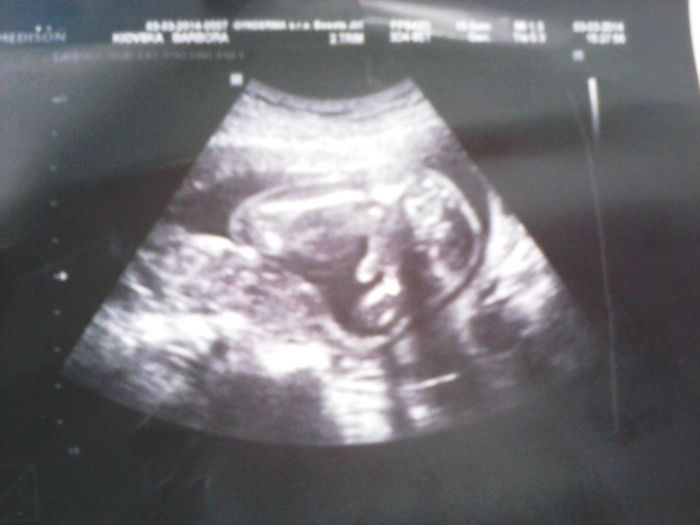

no tam kde je ta šipka tak to je prý penis? a to na těch stranách jsou stehna

[473297]já to tam prostě nevidím, na našem je krásné "kávové zrno", takže u nás je to na 100 % holčička